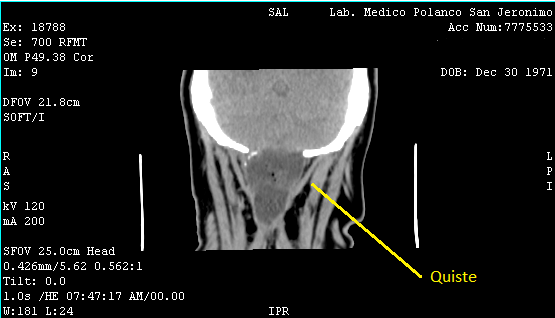

El doctor me pidió una tomografía: debido a mi historial quería asegurarse de que todo estuviera bien. En el estudio salió que tenía un poco de agua y aire, pero consideraba que eran cambios postquirúrgicos. Lo que no le gustaba eran las temperaturas que no cedían y que los dolores de cabeza iban en aumento, así que me citó en el hospital únicamente para tomar una muestra del agua y descartar que fuera resultado de una nueva infección.